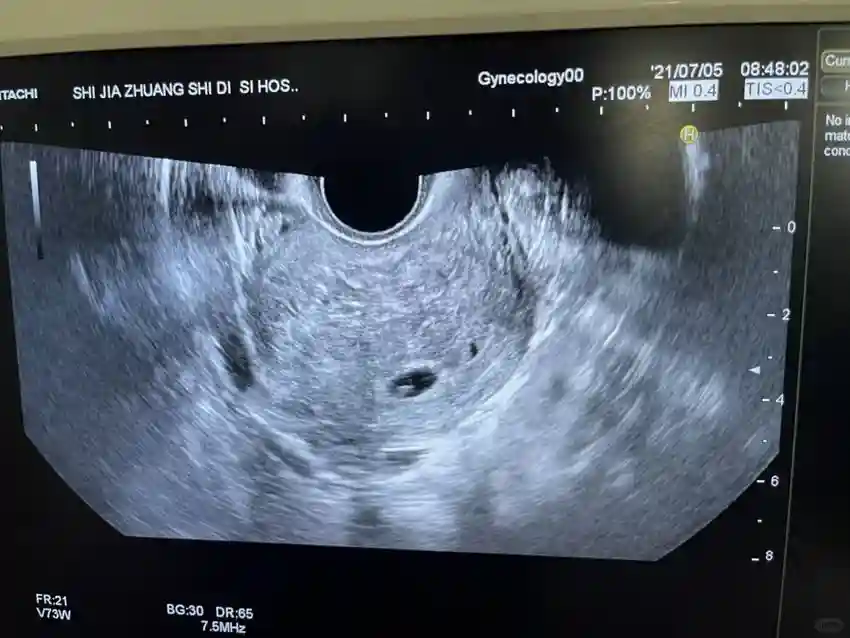

在移植前,我做了宫腔镜检查,因为我知道之前的流产可能会影响子言。之后又经过了三个月的子宫调理,才进行了移植,以免出现意外情况。第一次移植成功怀孕了,这让我们欣喜若狂,但是我们也知道这只是开始,需要保胎。现在已经过了3个月,我每天都在努力控制自己的意志力,希望宝宝能够顺利出生。